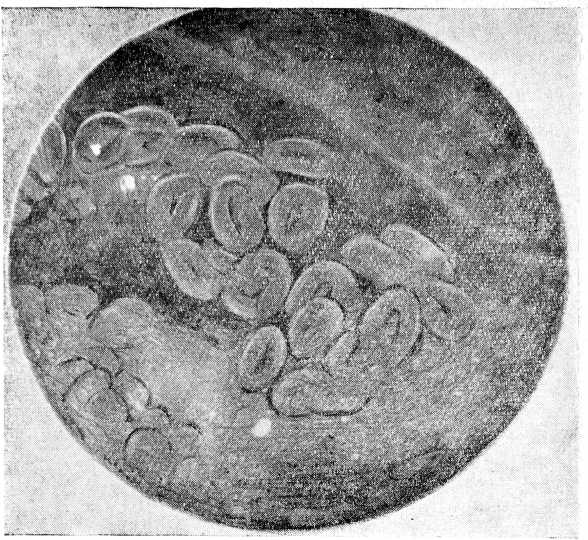

Микрофото № 1. Личинки Strongyloides stercoralis в пузырной желчи

Анализ крови 13/1 1953 г.: эр.— 4 310 000, гем.— 55%, ц. п.— 0,6, Л.— 5000, п.— 2, с.— 81, лимф.— 17, РОЭ — 40 мм в час. 23/II — при исследовании дуоденального 'содержимого обнаружены личинки Strongyloides stercoralis.